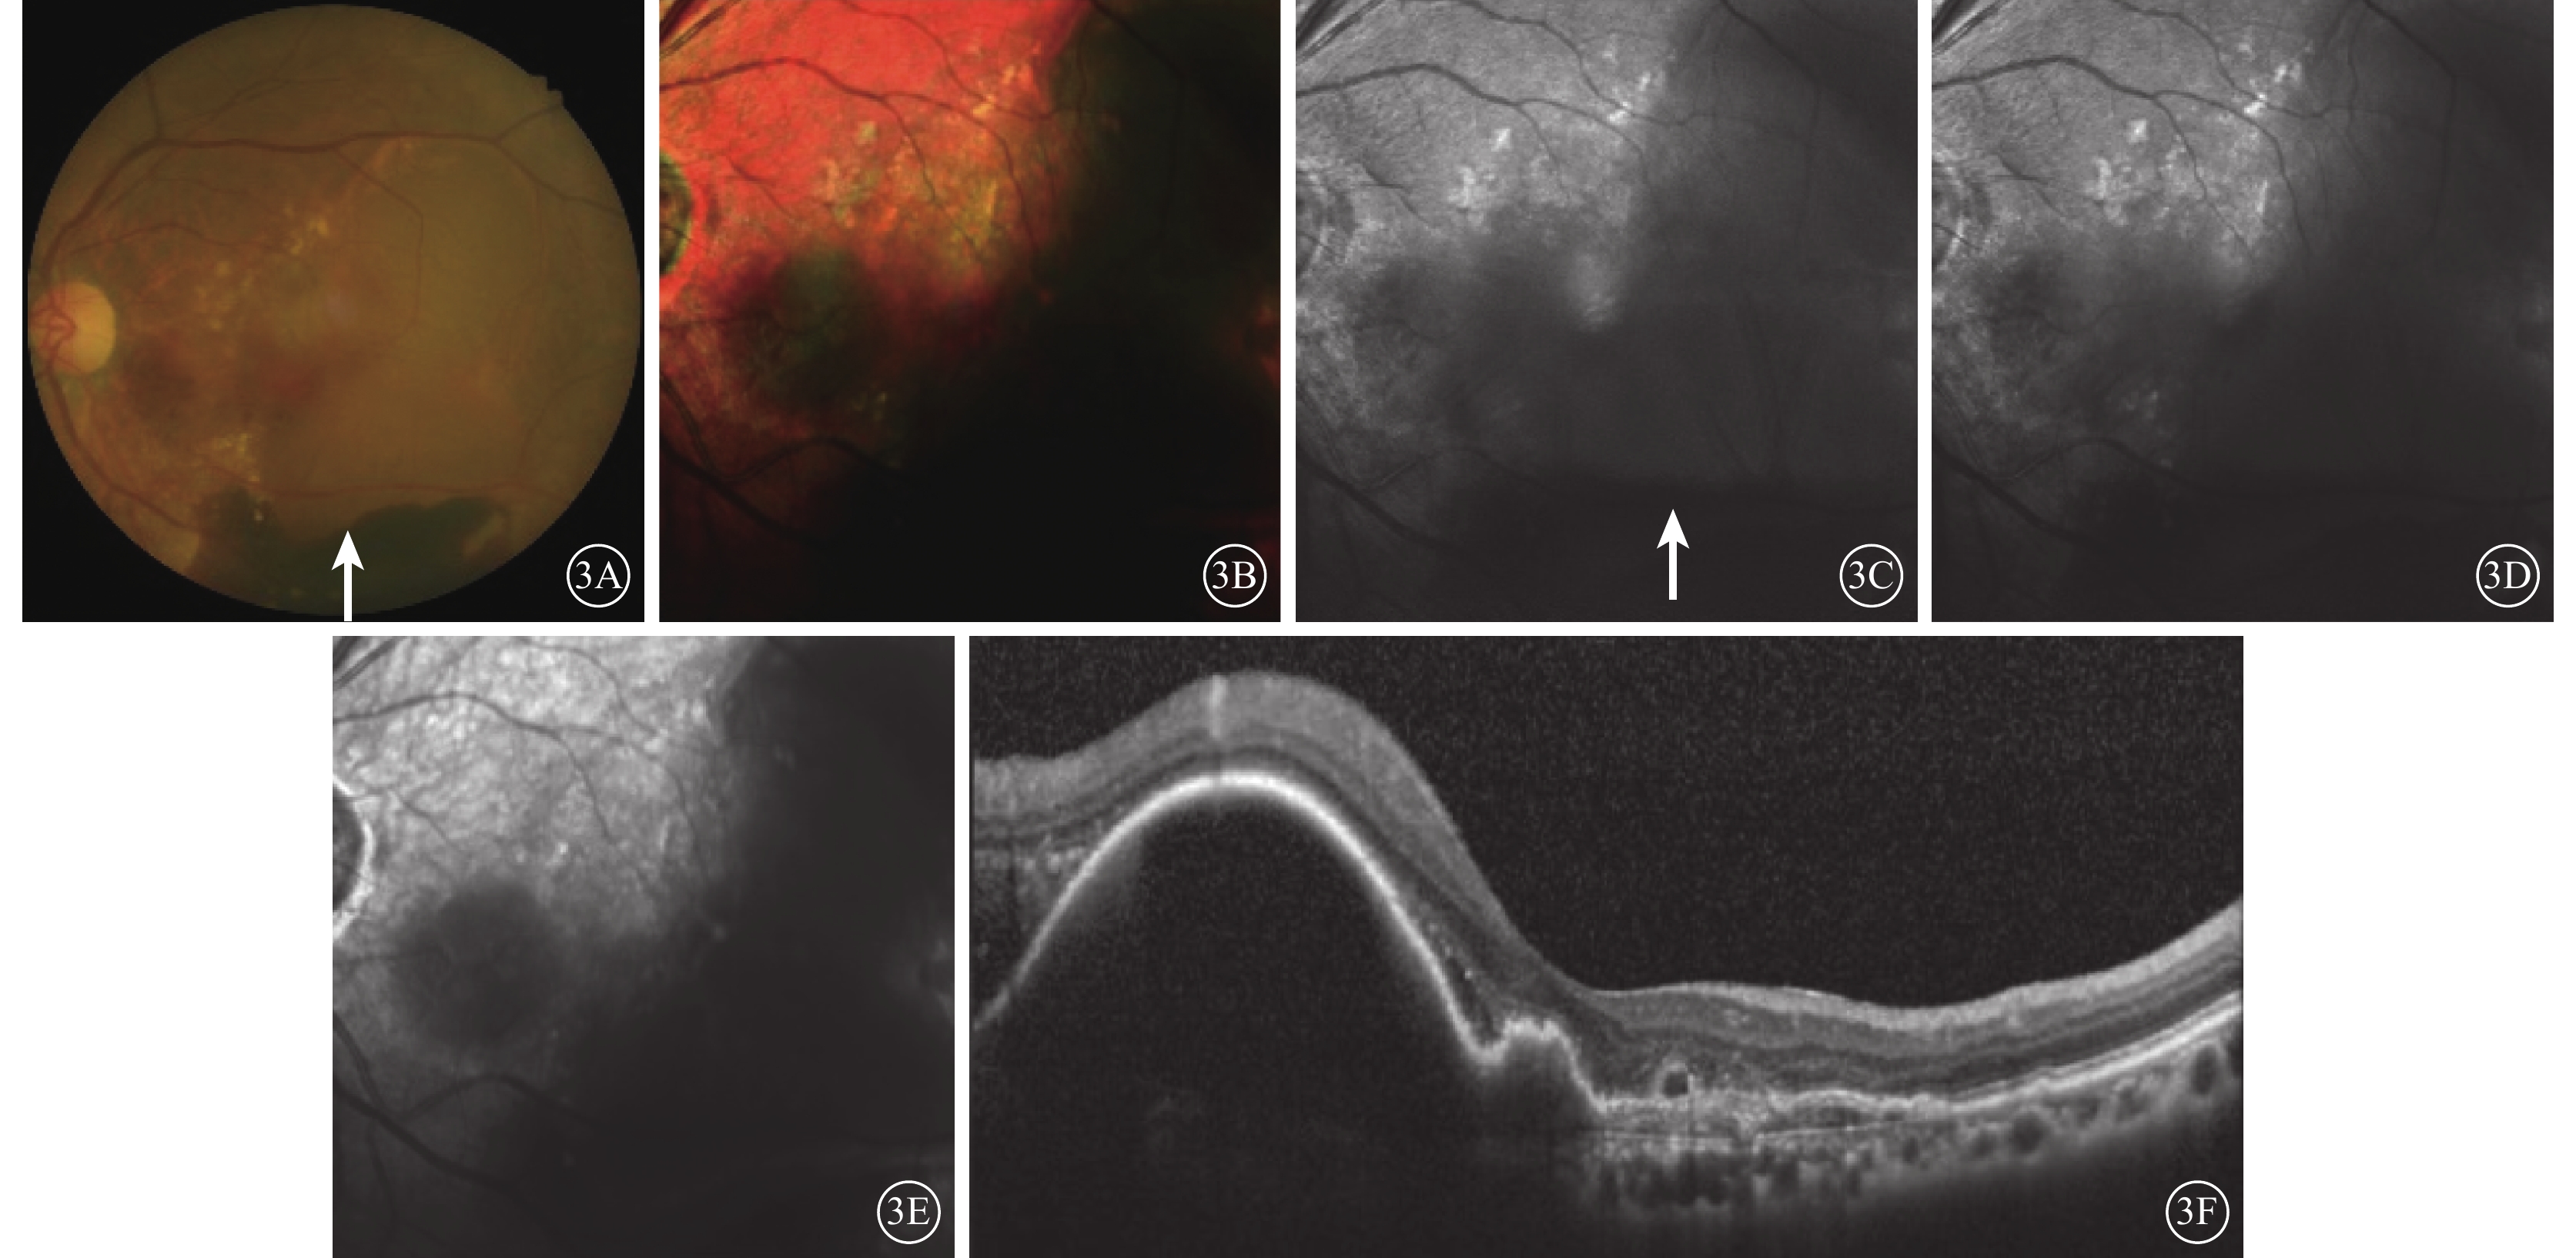

典型的漿液性PED在眼底彩色照相中表現為圓形或橢圓形的病灶,顏色較周圍正常視網膜組織偏暗,可伴黃白色滲出(圖2A);在cSLO成像中表現為圓形或橢圓形的綠色病灶(圖2B~2E),藍光反射、綠光反射中病灶稍弱反射,紅外反射中病灶反射最弱,與HD-OCT觀察到的PED位置一致(圖2F)。

典型的漿液性PED在眼底彩色照相中表現為圓形或橢圓形的病灶,顏色較周圍正常視網膜組織偏暗,可伴黃白色滲出(圖2A);在cSLO成像中表現為圓形或橢圓形的綠色病灶(圖2B~2E),藍光反射、綠光反射中病灶稍弱反射,紅外反射中病灶反射最弱,與HD-OCT觀察到的PED位置一致(圖2F)。

本研究結果顯示,PCV的漿液性PED在cSLO偽彩圖中表現為綠色或深綠色病灶,在紅外反射中呈現明顯弱反射暗區,藍光反射和綠光反射較弱。該觀察結果與Tan等[10]描述一致。而出血性PED則表現為深紅色病灶,綠光反射、藍光反射和紅外反射均呈現明顯弱反射。因為激光成像的原理是依靠不同波長激光而獲得不同層次的視網膜成像,藍光反射、綠光反射和紅外反射分別呈現視網膜淺層、中層和深層的結構。炫彩成像的過程中,依據眼底不同病變對不同波長的激光吸收、反射和透射的程度不同,顯示為相應波長激光反射的綜合圖像:藍光反射強度對應藍色成分,綠光反射強度對應綠色成分,而紅外反射強度對應紅色成分,3種反射的相對強弱決定病灶的顏色。水對光譜中的紅外部分表現出強烈的吸收,因而積液、水腫在紅外反射圖像中顯示為明顯的弱反射。因此,漿液性PED在紅外反射中呈現明顯暗區。紅外光被吸收多,反射弱;藍光和綠光吸收少,反射相對較強。并且,PED向視網膜內層隆起,病灶位于綠光反射區間,因此漿液性PED呈現綠色。血液對420~575 nm的光譜吸收率最高,反射弱;而紅外光吸收率最低,反射強[11]。因此,出血性PED在藍光反射和綠光反射出現明顯弱反射;炫彩成像中,藍光、綠光吸收多,反射弱;紅外光吸收少,相對反射較強,因此呈現紅色病灶。

本研究結果顯示,PCV的漿液性PED在cSLO偽彩圖中表現為綠色或深綠色病灶,在紅外反射中呈現明顯弱反射暗區,藍光反射和綠光反射較弱。該觀察結果與Tan等[10]描述一致。而出血性PED則表現為深紅色病灶,綠光反射、藍光反射和紅外反射均呈現明顯弱反射。因為激光成像的原理是依靠不同波長激光而獲得不同層次的視網膜成像,藍光反射、綠光反射和紅外反射分別呈現視網膜淺層、中層和深層的結構。炫彩成像的過程中,依據眼底不同病變對不同波長的激光吸收、反射和透射的程度不同,顯示為相應波長激光反射的綜合圖像:藍光反射強度對應藍色成分,綠光反射強度對應綠色成分,而紅外反射強度對應紅色成分,3種反射的相對強弱決定病灶的顏色。水對光譜中的紅外部分表現出強烈的吸收,因而積液、水腫在紅外反射圖像中顯示為明顯的弱反射。因此,漿液性PED在紅外反射中呈現明顯暗區。紅外光被吸收多,反射弱;藍光和綠光吸收少,反射相對較強。并且,PED向視網膜內層隆起,病灶位于綠光反射區間,因此漿液性PED呈現綠色。血液對420~575 nm的光譜吸收率最高,反射弱;而紅外光吸收率最低,反射強[11]。因此,出血性PED在藍光反射和綠光反射出現明顯弱反射;炫彩成像中,藍光、綠光吸收多,反射弱;紅外光吸收少,相對反射較強,因此呈現紅色病灶。